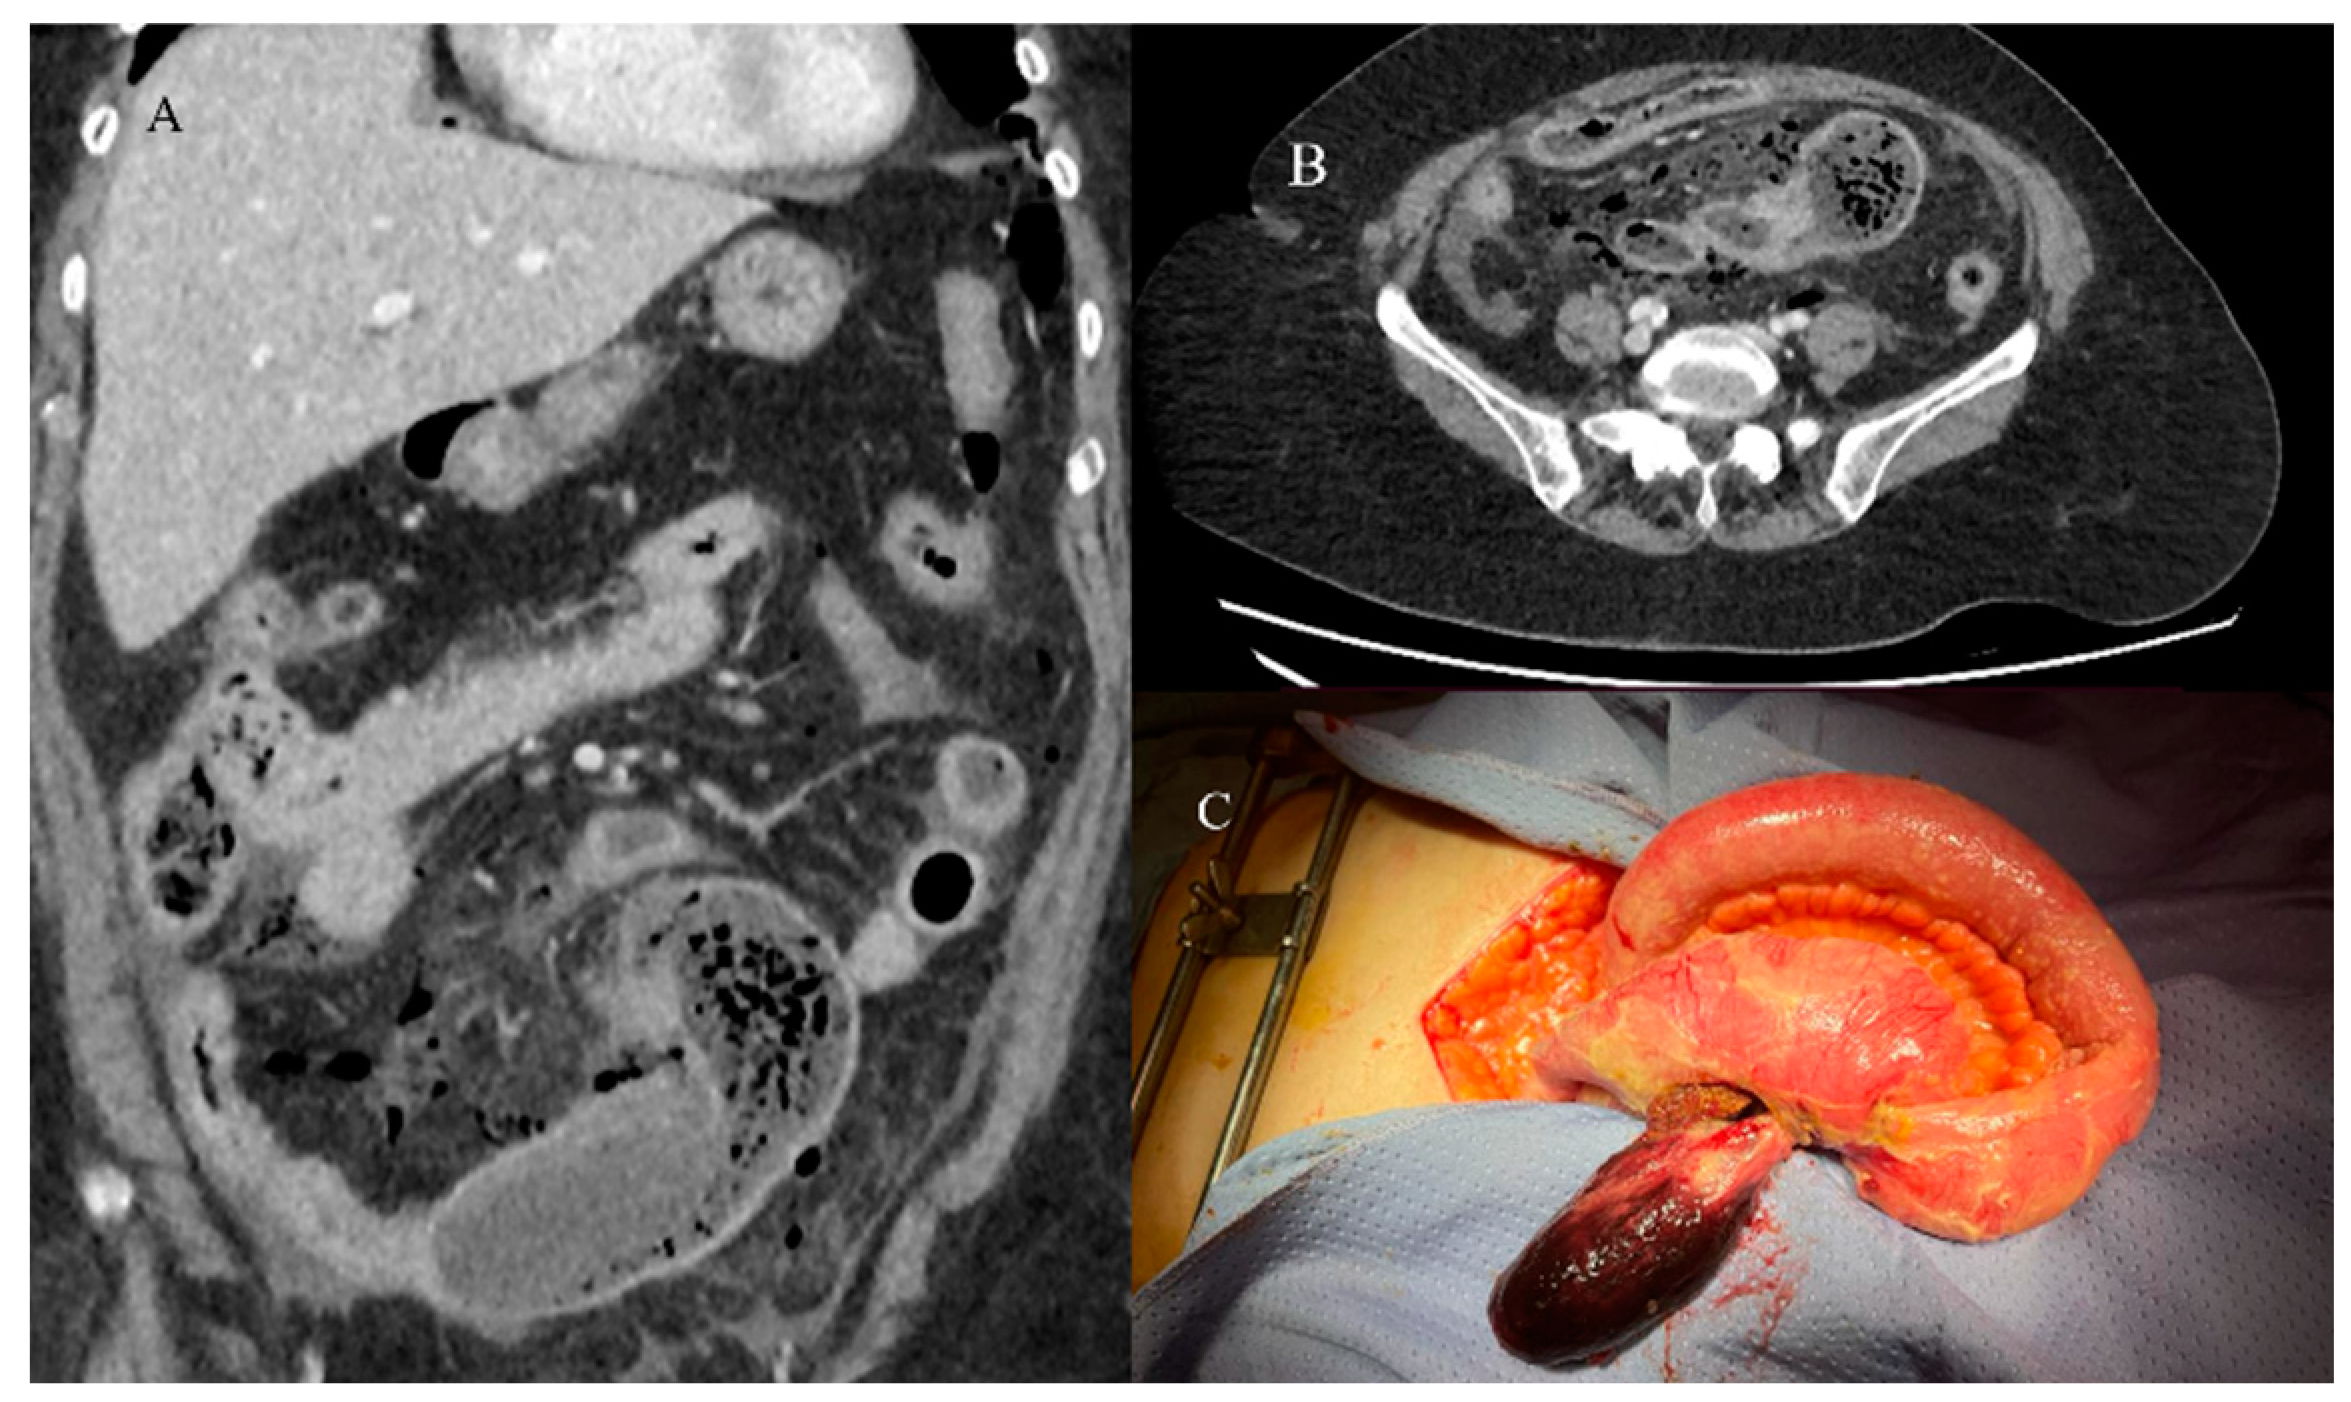

- Tuca, A.; Guell, E.; Martinez-Losada, E.; Codorniu, N. Malignant bowel obstruction in advanced cancer patients: Epidemiology, management, and factors influencing spontaneous resolution. Cancer Manag. Res. 2012, 4, 159–169. [Google Scholar] [CrossRef]

- Nelms, D.W.; Kann, B.R. Imaging modalities for evaluation of intestinal obstruction. Clin. Colon. Rectal Surg. 2021, 34, 205–218. [Google Scholar] [CrossRef]

- Paulson, E.K.; Thompson, W.M. Review of small-bowel obstruction: The diagnosis and when to worry. Radiology 2015, 275, 332–342. [Google Scholar] [CrossRef] [PubMed]

- Chao, T.C.; Chao, H.H.; Jan, Y.Y.; Chen, M.F. Perforation through small bowel malignant tumors. J. Gastrointest. Surg. 2005, 9, 430–435. [Google Scholar] [CrossRef] [PubMed]